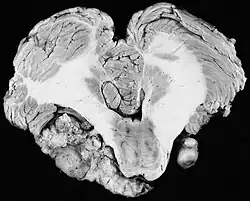

![]() | |

| 3D rendering of a vestibular schwannoma | |